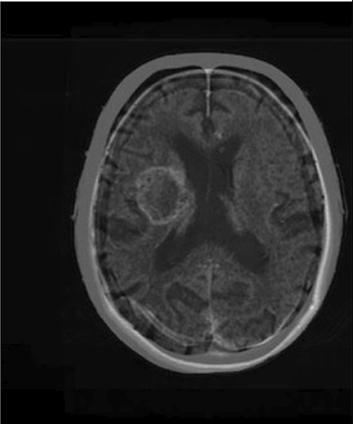

Table 6 Fused image output.

From: Multimodal medical image fusion combining saliency perception and generative adversarial network